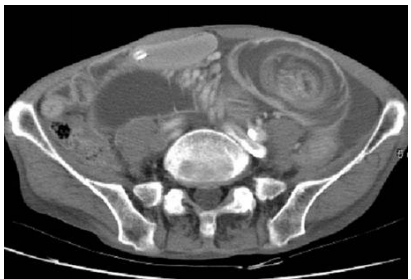

72 病人主訴腹脹、反胃、腹部悶痛。腹部電腦斷層檢查呈現腸阻塞如附圖。下列造成此病人腸阻塞的 原因,那一項最正確?

(A)phytobezoar (B)intussusception (C)inguinal hernia (D)volvulus